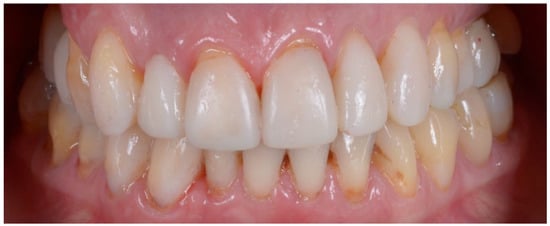

2.2. Clinical Example

2.3. Outcome Achieved

| Disharmonious smile | Yes | No |

| Dyschromia, dysmorphia, abrasions, and erosions of teeth | Yes | No |

| Anterior crowding in the upper arch | Yes | No |

| Anterior crowding in the lower arch | Yes | No |

| Upper transverse discrepancy | Yes | No |

| Presence of buccal corridors or black tunnels | Yes | No |

| Curve of Spee alteration | Yes | No |

| Curve of Wilson alteration | Yes | No |

| Functional movements with altered guides | Yes | No |

| Pain and/or noise ATM | Yes | No |